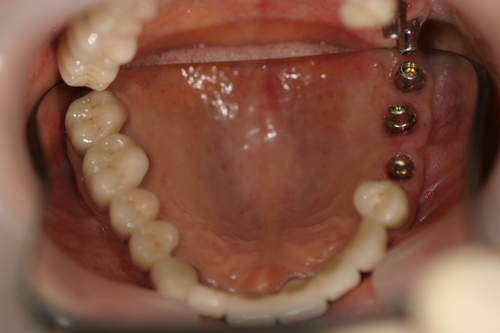

この患者様は、右上の奥歯の歯茎から出血してくるとのことで来院されました。歯周組織検査とレントゲンで診断を行った結果、重度の歯槽膿漏が認められ、保存不可能の為、抜歯になると伝えたところ、入れ歯は絶対に嫌だと言われたので、インプラント治療となりました。CT撮影を行ったところ、上顎洞底までの距離が3ミリ程度しかなかったのですが、骨が固く、フィクスチャーの一次固定が良好だったので、開窓法による上顎洞底挙上術とフィクスチャーの埋入を同時に行いました。約10カ月後に二次手術を行い、上部構造をセットしました。また、右下の臼歯部のブリッジにも大きな二次カリエスが認められ、7番の遠心根が抜歯になり、6番、7番にインプラント治療をしました。